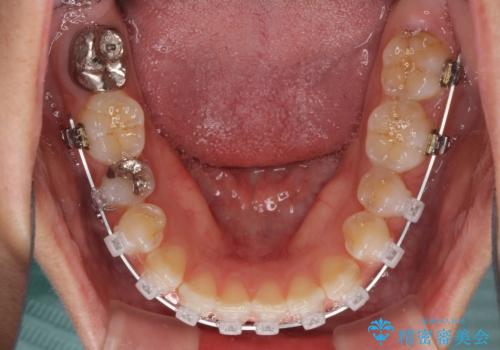

- クリアブラケット

下の前歯が上の前歯を突き上げるように咬合するため、咬み合わせの位置を改善しながら隙間を閉じていきました。

元々の歯並びが悪くなかったため、9ヶ月で綺麗に仕上がりました。

すきっ歯は後戻りを起こしやすいため、上下ともに歯の裏側を細いワイヤーで固定した上で、リテーナーのマウスピースを装着していただいています。